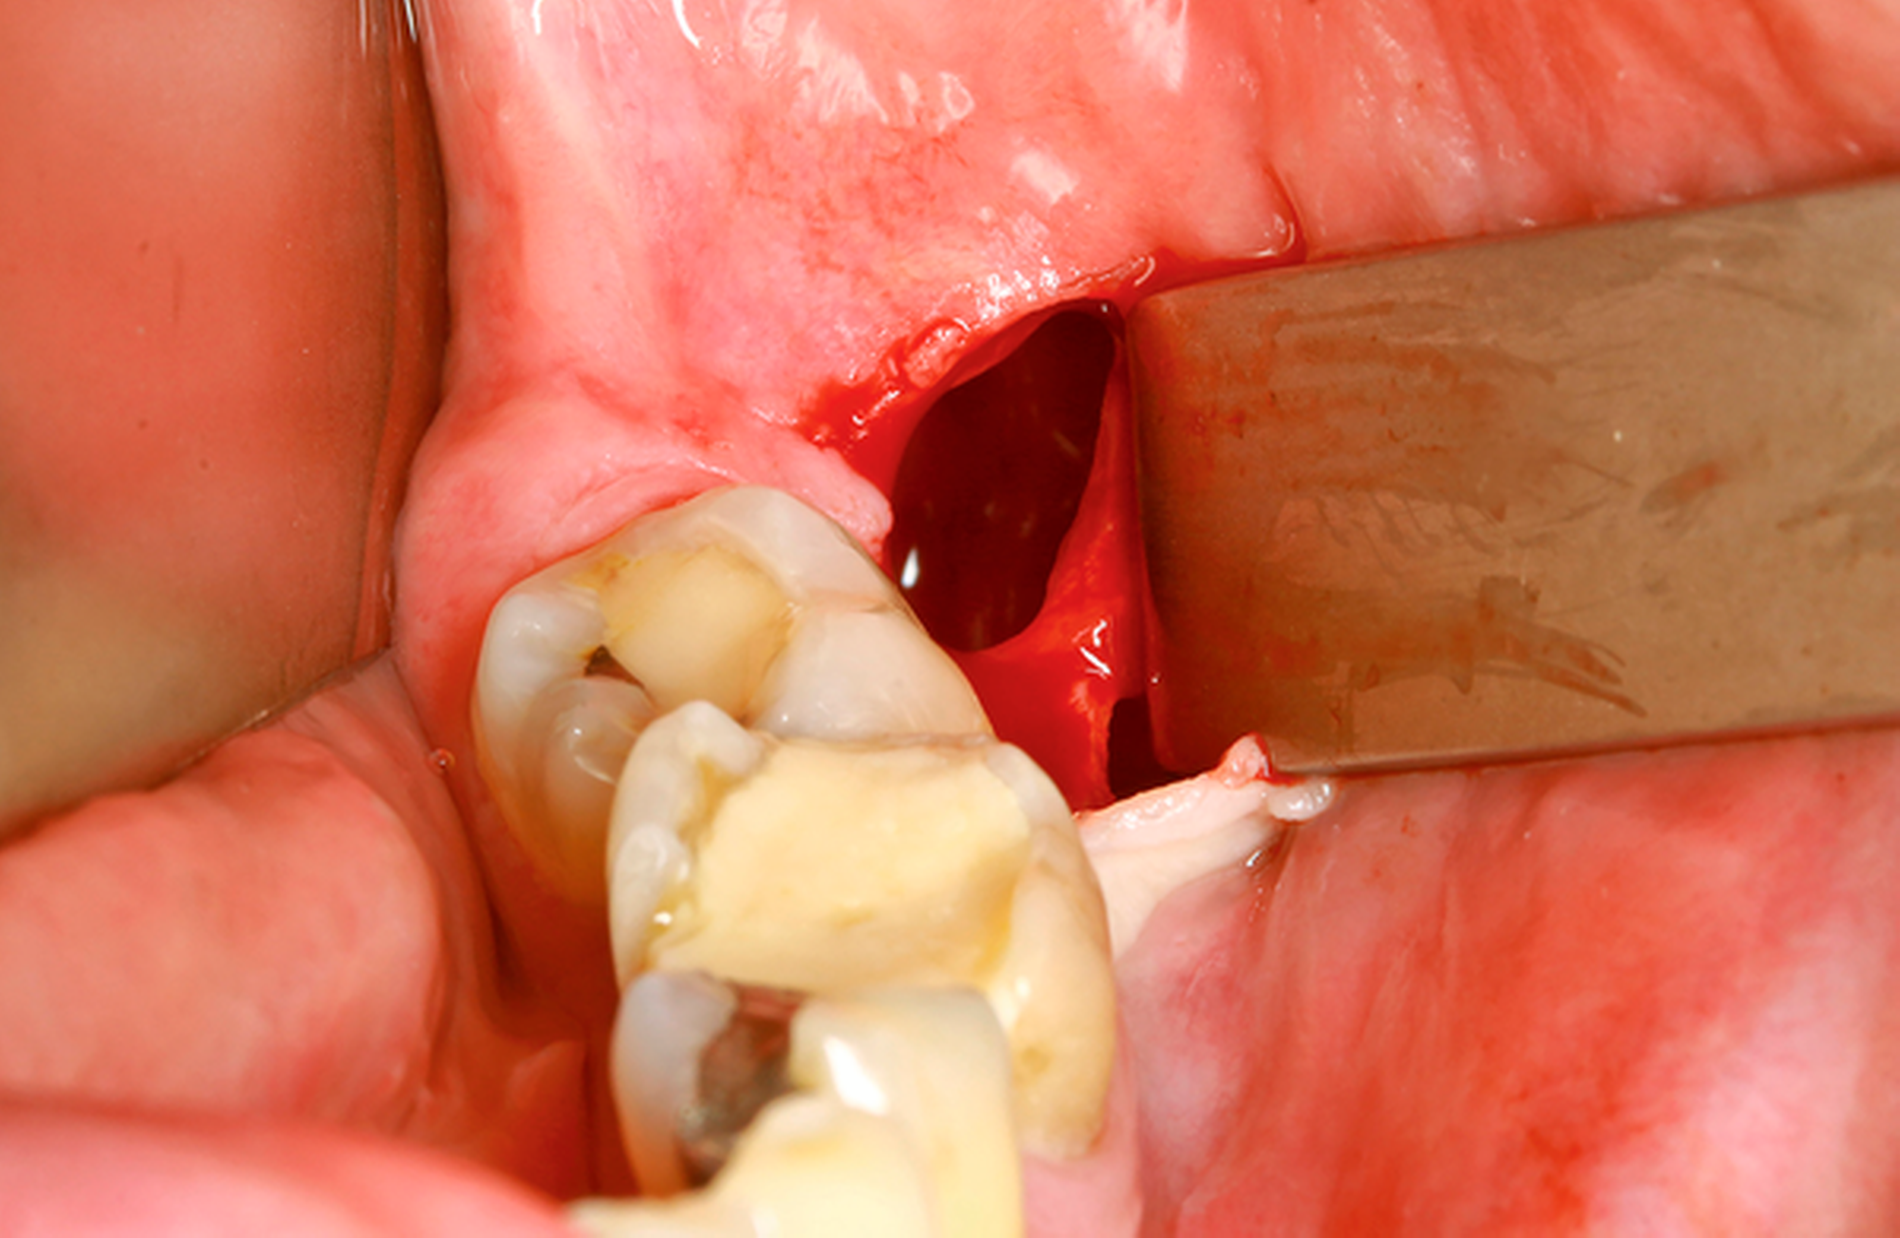

Ein 52-jähriger Patient stellte sich mit Überweisung und Bitte um Therapie einer zystischen Raumforderung im Bereich des rechten Kieferwinkels über unser MVZ vor (Abbildung 6a). Aufgrund der erhöhten Frakturgefahr bei einem weit nach kaudal verlagerten Zahn 48 entschied sich der Patient nach entsprechender Aufklärung für das mehrzeitige Verfahren mittels Zystostomie. Die Versorgung erfolgte in diesem Fall mit einem nicht zahngetragenen Obturator, der lediglich mittels eines Gingivaschildes ins Vestibulum eingelagert war. Der Patient kam damit nach initialer individueller Einpassung gut zurecht. Die radiologischen Kontrollen erfolgten nach histologischer Sicherung einer follikulären Zyste halbjährlich zur Sicherung des Therapieerfolgs. Bei nach elf Monaten deutlich regredientem Befund konnte die Zystektomie und operative Entfernung des Zahnes 48 in ambulanter Allgemeinanästhesie durchgeführt werden, wobei keine perioperativen Komplikationen auftraten (Abbildung 6b). Besonders hervorzuheben ist die Wanderungsbewegung des Zahnes 48 nach koronal. Abbildung 6c zeigt die knöcherne Konsolidierung des Defekts sieben Monate postoperativ bei Beschwerdefreiheit. Bezüglich des vitalen Zahns 47 (ohne Lockerung) wurde eine prothetische Versorgung durch den Hauszahnarzt empfohlen.